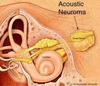

Primeira crise de Cefaleia em Salvas + Sinal Focal, deve-se indicar EXAME DE IMAGEM para…

Excluir cefaléias secundárias…

- HSA.

- Trombose de seio cavernoso.

- Meningite.